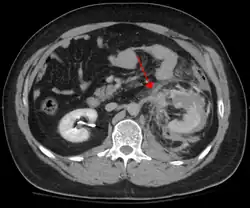

Blunt abdominal trauma

Blunt abdominal trauma (BAT) represents 75% of all blunt trauma and is the most common example of this injury.[3] Seventy-five percent of BAT occurs in motor vehicle crashes,[4] in which rapid deceleration may propel the driver into the steering wheel, dashboard, or seatbelt,[5] causing contusions in less serious cases, or rupture of internal organs from briefly increased intraluminal pressure in the more serious, depending on the force applied. Initially, there may be few indications that serious internal abdominal injury has occurred, making assessment more challenging and requiring a high degree of clinical suspicion.[6]

There are two basic physical mechanisms at play with the potential of injury to intra-abdominal organs: compression and deceleration.[7] The former occurs from a direct blow, such as a punch, or compression against a non-yielding object such as a seat belt or steering column. This force may deform a hollow organ, increasing its intraluminal or internal pressure and possibly leading to rupture.[7]

Deceleration, on the other hand, causes stretching and shearing at the points where mobile contents in the abdomen, like the bowel, are anchored. This can cause tearing of the mesentery of the bowel and injury to the blood vessels that travel within the mesentery. Classic examples of these mechanisms are a hepatic tear along the ligamentum teres and injuries to the renal arteries.[7]

When blunt abdominal trauma is complicated by 'internal injury,' the liver and spleen (see blunt splenic trauma) are most frequently involved, followed by the small intestine.[8]